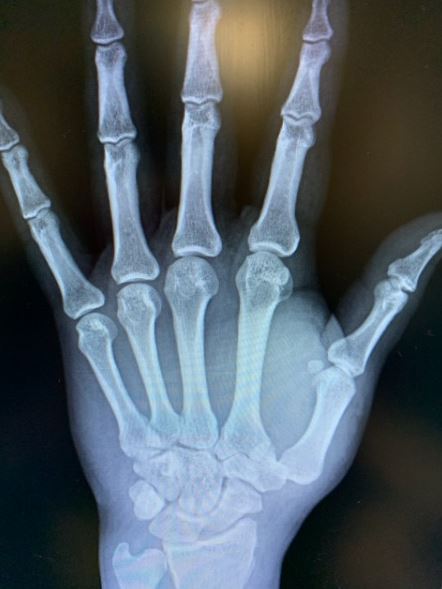

What’s the Diagnosis? Gepost op 27 september 202023 september 2020 door netwerkvsseh What’s the Diagnosis? By Dr. Valeria Wu @emdaily.cooperhealth.org Dit delen: Delen op X (Opent in een nieuw venster) X Share op Facebook (Opent in een nieuw venster) Facebook Delen op LinkedIn (Opent in een nieuw venster) LinkedIn E-mail een link naar een vriend (Opent in een nieuw venster) E-mail Afdrukken (Opent in een nieuw venster) Print Vind-ik-leuk Aan het laden... Gerelateerd